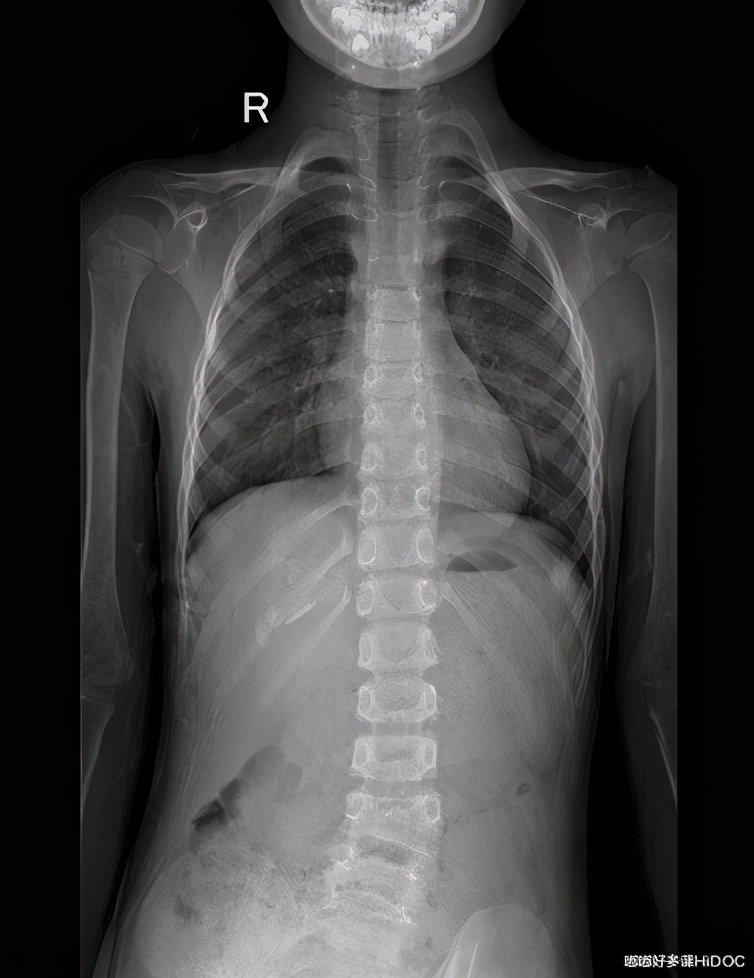

先天性脊柱侧弯站立、躯干前屈图。这例弯曲程度已比较大,一般孩子达不到这种程度,家长如有怀疑,可带孩子到医院拍片就诊。

三、影像学检查最为精准

自测方法存在一定的不准确性,若要精确,各位家长带孩子来医院骨科,做X线、CT、核磁共振(MRI)等影像学检查来观测孩子的确切情况。

以上两例的脊柱侧弯状况在X光片中已很明显,然而孩子外观的异常肉眼感受并不强烈。如果家长有这个担心,做个检查会更放心。